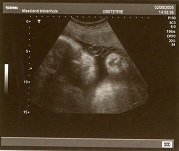

Als je zwanger bent, moet je naar de dokter voor controle. Je gaat hiervoor naar speciale doktoren; de verloskundige en de gynaecoloog. Zij maken onder anderen een echo van de baby.

Dat is een soort foto van de foetus. Een apparaat dat hoge geluiden produceert wordt gebruikt om beelden op een monitor te projecteren. Net als een radar vangt het apparaat de echo van de geluidsgolven die naar de foetus gezonden worden op en zet deze om in beelden. Zo kan de foetus onderzocht worden en kunnen de ouders zien of het een jongentje of een meisje is.